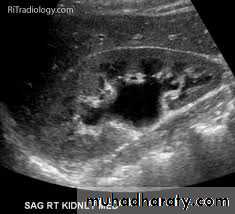

*Hydronephrosis:-dilated pelvicalyceal system on US